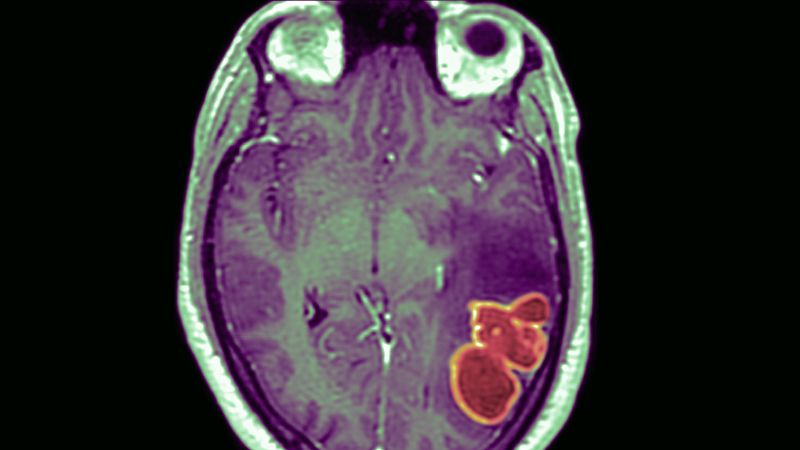

Cases of brain abscesses in American children have surged to new heights following the easing of pandemic restrictions, according to reports from the CDC. These abscesses, which are relatively rare but dangerous, are typically caused by bacteria or fungi entering the brain through respiratory infections such as COVID-19, the flu, or sinusitis. The CDC emphasizes the importance of children staying up-to-date with their vaccinations to prevent these infections. While cases have fallen since a peak in December 2022, they remain above the baseline maximum, indicating the need for continued monitoring and vigilance.